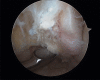

Material and methods: Of the 22 patients who were treated; 18 males and 4 females, and aged from 17-42 years (mean 28 years). All patients presented a history of more than three ankle sprains in the last two years and presented positive anterior drawer and talar tilt test of the ankle in the physical examination. We perform an anterior arthroscopy of the ankle in order to treat asociated disease and then we performed "All inside¨ lateral ligament repair through two portals (anteromedial and anterolateral) using an anchor knotless suture.